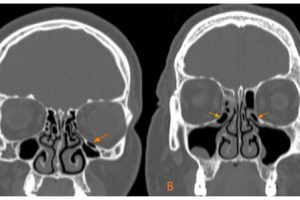

From your question it sounds like you have been seeing somebody for sinus problems. As you know,  the sinuses are normally air filled cavities, mostly in the bones of your face. Some of the cavities, like the maxillary sinuses in your cheeks, are big, and some are smaller. Haller cells are just tiny cavities between the maxillary and ethmoid sinuses. They are not always present and when they are there they are usually not a problem unless they are obstructing drainage of the other sinuses into the nose.

There is nothing specific pertaining to Haller sells that distinguishes them from other sinus cavities,, and certainly not in terms of their affect on the voice. Their main potential negative affect is that they can get in the way of normal ventilation to the adjacent sinuses.

This is where sinus occlusion, including the tiny Haller cell,  may play a role. My concern with your question, is that may have told you that you have a blocked ( or obstructing) Haller cell and this needs to be treated to improve your voice. An isolated small sinus cell should not significantly affect your voice, and if you were considering surgery for this, I would advise a second opinion.